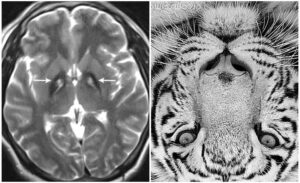

La neurodegeneración asociada a pantotenato quinasa, neurodegeneración por acumulación de hierro tipo 1, o síndrome de Hallervorden-Spatz es una entidad neurológica con herencia autosómica recesiva que aparece desde la infancia. Clínicamente se caracteriza por la presencia de demencia, alteraciones de la postura y el tono muscular, síntomas extrapiramidales y ataxia. Se debe a una mutación del gen que codifica la proteína pantotenato kinasa (PANK2), lo que da lugar a un acumulo de hierro en los ganglios basales y que da una imagen característica de “ojos de tigre” en Resonancia Magnética.